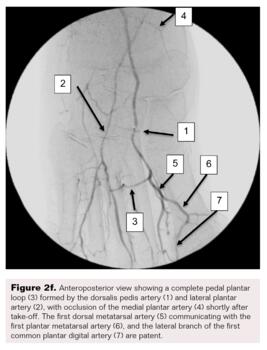

A right lower-extremity angiogram was performed using ultrasound guidance for antegrade access of the proximal superficial femoral artery (Figure 2A). Fluoroscopic acquisition demonstrated no significant disease in the superficial femoral artery (Figure 2B) and popliteal artery (Figure 2C), with no significant stenosis seen in the anterior tibial artery, PTA, and peroneal artery (Figure 2D). Pedal angiography demonstrated a complete pedal-plantar loop formed by the DPA and the lateral plantar artery (LPA) (Figure 2F).

However, the entirety of the medial plantar artery (MPA) distribution was chronically occluded shortly after take-off (Figure 2E and Figure 2F). Super-selective angiography revealed chronic total occlusion of the medial branch of the first common plantar digital artery arising from the first plantar metatarsal artery (Figure 2G). Angiography also revealed an occluded accessory branch arising medially from the superficial branch of the MPA.

The anatomy of the arteries supplying the hallux is complex, with variants being common. In this patient, an atypical accessory branch arising from the superficial branch of the MPA was present. While the arterial anatomy of hallux-supplying arteries and its corresponding variants are not readily discussed in recent literature, certain textbooks do depict an accessory branch arising from the superficial branch of the MPA.2 The accessory branch of this patient, in particular, communicated with the first dorsal metatarsal artery arising from the DPA (Figure 2F) and the superficial branch of the MPA communicated with the medial branch of the first common plantar digital artery arising from the LPA (Figure 4C). In general, using the angiosome concept, the blood supply to the hallux consists of 3 main avenues: (1) the first dorsal metatarsal branch arising from the DPA; (2) the plantar digital arteries arising from the first plantar metatarsal artery, which is a branch of the LPA; and (3) the superficial branch of the MPA.3,4 The latter 2 sources of blood supply were absent in this case.